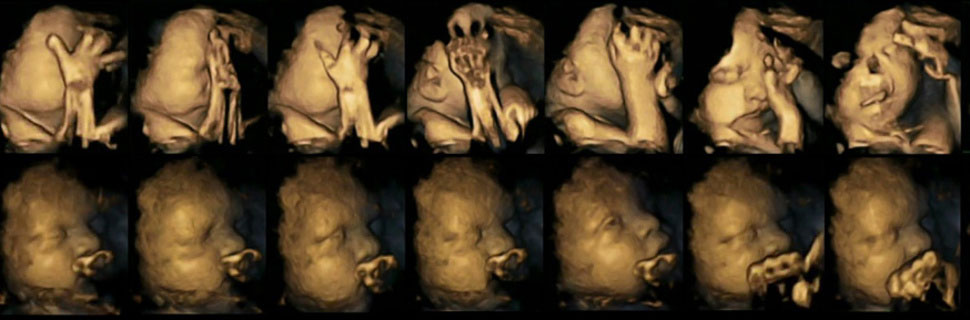

A continuación se presentan una serie de ecografías en 4-D de dos fetos diferentes. La fila superior muestra un feto cuya madre está fumando. La fila inferior muestra el feto de una madre que no fuma.

Los investigadores encontraron que los fetos cuyas madres eran fumadoras mostraban una tasa significativamente mayor de movimientos de la boca frente a la tasa normal de movimientos que se esperan de un feto durante el embarazo.

Los investigadores sugirieron que la razón de esto podría ser que el sistema nervioso central fetal, que controla los movimientos en general y los movimientos faciales en particular, no se desarrolló a la misma velocidad y de la misma manera en los fetos de las madres que no fumaron durante el embarazo.